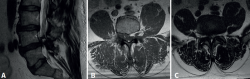

Figura 4. Resonancia magnética del fémur izquierdo. A: corte coronal en secuencia STIR, con masa de partes blandas de gran tamaño con afectación diafisaria femoral; B: corte axial en secuencia T2, con masa heterogénea con áreas de necrosis central; C: corte axial en secuencia T1 con supresión grasa, con compromiso del trayecto del nervio ciático por la masa tumoral.